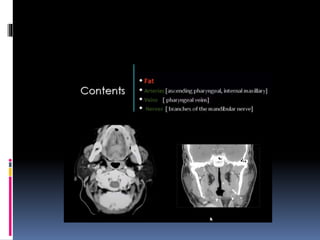

 Coronal sections of the nasopharynx show the-

eustachian tube opening, torus tubaris. Fossa of

rosenmuller and the adenoids, if present.

 Asymmetry of the Fossa of rosenmuller should

be looked for.

 The foramen ovale is seen laterally in the

greater wing of sphenoid

Contents of Foramen Ovale –

1. Mandibular nerve

2. Accessory meningeal artery

3. Lesser petrosal nerve.

4.Emissary veins

Widening of Foramen Ovale may be seen in

nasopharyngeal angiofibroma.

 Destruction of Foramen Ovale may be seen in

carcinoma nasopharynx.